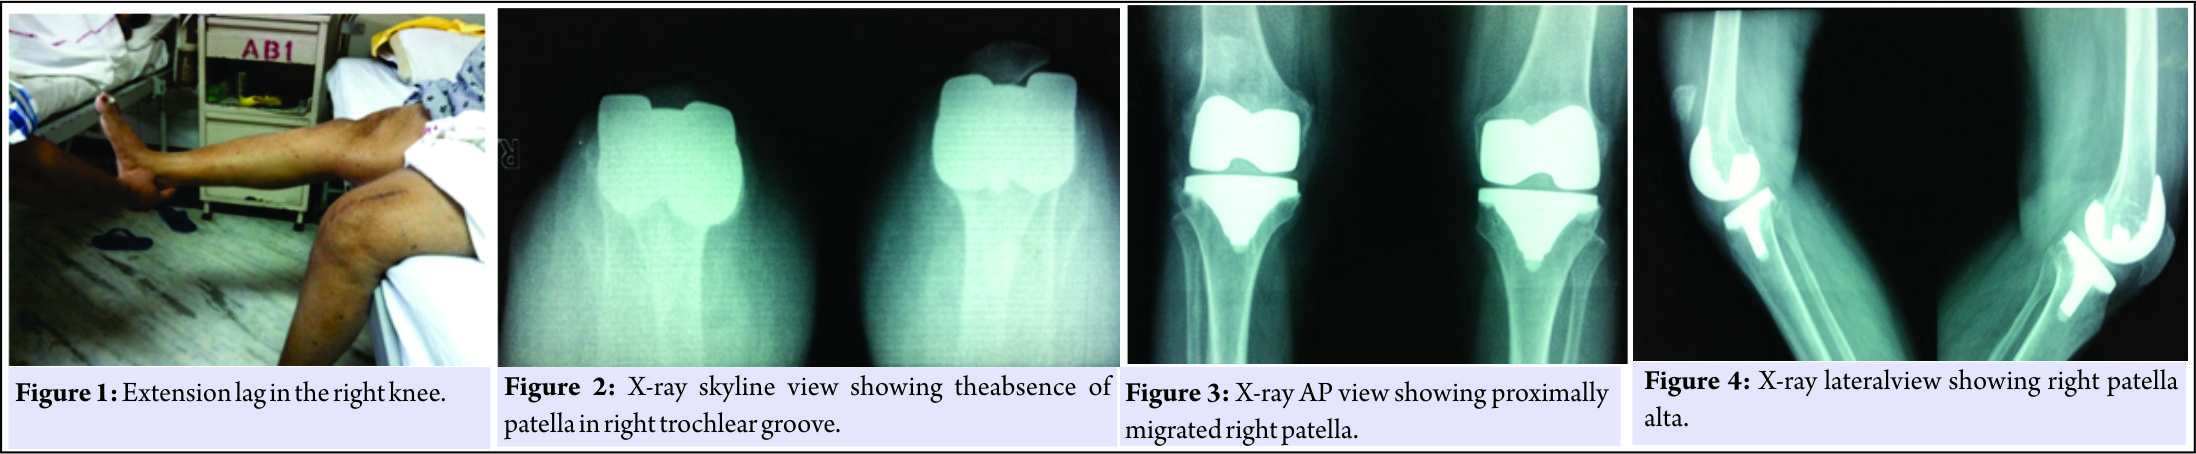

A 69-year-old woman underwent bilateral total knee replacement for symptomatic Grade III osteoarthritis of both the knees. The surgery was performed using a midline skin incision and midvastus approach. A cemented cruciate substituting posterior stabilized implant(Stryker NRG Scorpio, right knee femoral component size 4, tibial component size 4,and insert thickness 8 mm and left knee femoral component of size 5, tibial component size 4, and insert thickness 10 mm) was used. The patella was everted during surgery as usual and patelloplasty was done. She recovered well in the post-operative period,attaining range of motion from 0 to 90° by the end of 1st week of surgery, and could walk comfortably without support 4 weeks after the surgery.She did not report until about 6 months after surgery when she started having difficulty in walking with right knee and in getting up from sitting position.She did not have any pain and did not report any trauma. On examination, she had an extension lag of 30° and could flex up to 110° (Fig. 1). The knee was not warm orerythematous, but patella was located higher than normal. There was minimal tenderness around patellar tendon and tibial tuberosity, and x-ray revealed patella alta on the right side which led to the diagnosis of patellar tendon avulsion (Fig. 2, 3, 4). On exploration, patellar tendon was found to be avulsed from tibial tuberosity with 8–10 cm proximal migration of patella and extensive fibrosis in between (Fig. 1). After debridement, the patella was mobilized down to its normal position only with aquadriceps snip.The semitendinosus tendon was harvested through a small incision over the pes anserinus using tendon stripper, keeping its tibial attachment intact. One 6 mm wide tunnel was drilled horizontally into the tibial tuberosity and one transversely in the upper half of the patella. The free end of the harvested tendon was first made to pass through the tibial tunnel from medial to lateral direction and was then weaved through the patellar tendon remnant and fibrous tissue in a proximal direction toward patella. It was then made to pass through the patellar tunnel from lateral to medial end and was again weaved through the available scar tissue and carried distally to end just medial to the tibial tuberosity where it was stapled after tensioning at 30° of knee flexion (Fig. 5, 6, 7, 8).

The knee was not warm orerythematous, but patella was located higher than normal. There was minimal tenderness around patellar tendon and tibial tuberosity, and x-ray revealed patella alta on the right side which led to the diagnosis of patellar tendon avulsion (Fig. 2, 3, 4). On exploration, patellar tendon was found to be avulsed from tibial tuberosity with 8–10 cm proximal migration of patella and extensive fibrosis in between (Fig. 1). After debridement, the patella was mobilized down to its normal position only with aquadriceps snip.The semitendinosus tendon was harvested through a small incision over the pes anserinus using tendon stripper, keeping its tibial attachment intact. One 6 mm wide tunnel was drilled horizontally into the tibial tuberosity and one transversely in the upper half of the patella. The free end of the harvested tendon was first made to pass through the tibial tunnel from medial to lateral direction and was then weaved through the patellar tendon remnant and fibrous tissue in a proximal direction toward patella. It was then made to pass through the patellar tunnel from lateral to medial end and was again weaved through the available scar tissue and carried distally to end just medial to the tibial tuberosity where it was stapled after tensioning at 30° of knee flexion (Fig. 5, 6, 7, 8). We used non-absorbable sutures to secure and reinforce these mitendinosus tendon passing over the patellar tendon. An intraoperative flexion of 90 could be attained easily, without tension. Post-operative radiographs showed good restoration of the patellar height with a Caton–Deschamps index of 1 (Fig. 9,10,11). The patient was given a cylinder cast for 4 weeks and allowed full weight bearing. Atthe last follow-up of 2 years after the surgery, the range of motion was 0–110° with no extension lag and the patient was ambulatory without any support.